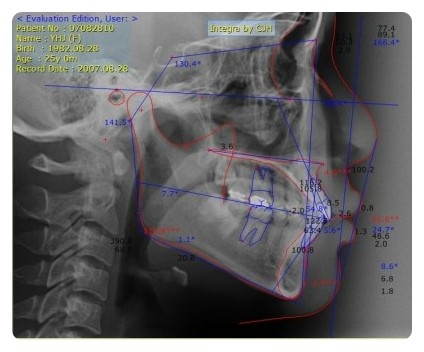

<v-ceph 프로그램으로 얼굴을 정밀하게 분석한 후 교정 결과를 예측>